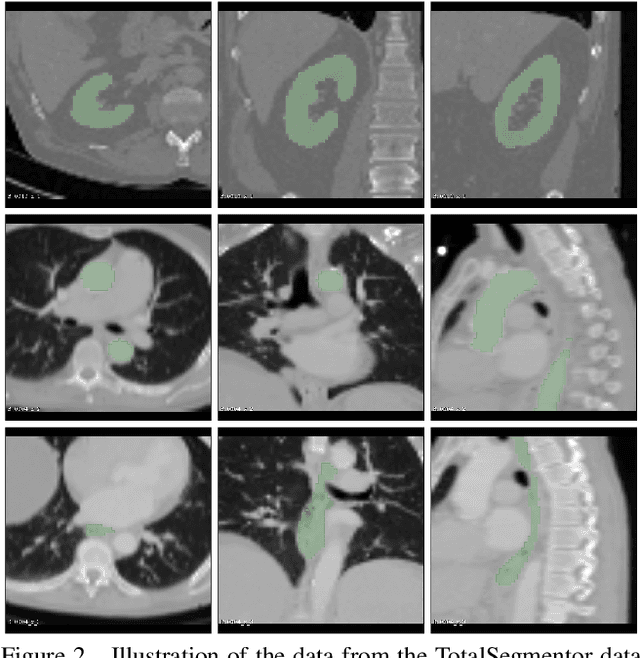

Abstract:This work presents a study on label noise in medical image segmentation by considering a noise model based on Gaussian field deformations. Such noise is of interest because it yields realistic looking segmentations and because it is unbiased in the sense that the expected deformation is the identity mapping. Efficient methods for sampling and closed form solutions for the marginal probabilities are provided. Moreover, theoretically optimal solutions to the loss functions cross-entropy and soft-Dice are studied and it is shown how they diverge as the level of noise increases. Based on recent work on loss function characterization, it is shown that optimal solutions to soft-Dice can be recovered by thresholding solutions to cross-entropy with a particular a priori unknown threshold that efficiently can be computed. This raises the question whether the decrease in performance seen when using cross-entropy as compared to soft-Dice is caused by using the wrong threshold. The hypothesis is validated in 5-fold studies on three organ segmentation problems from the TotalSegmentor data set, using 4 different strengths of noise. The results show that changing the threshold leads the performance of cross-entropy to go from systematically worse than soft-Dice to similar or better results than soft-Dice.